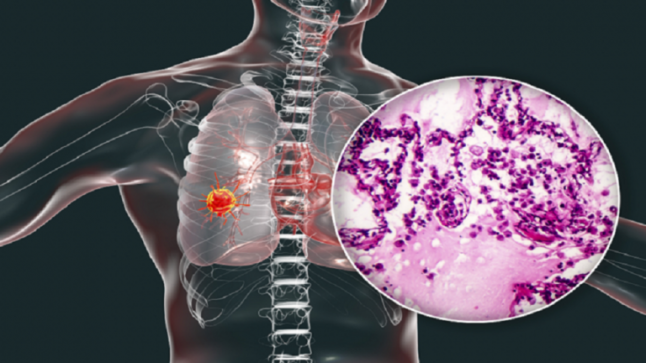

وتشير صحيفة The Sun، إلى أنه وفقا للخبراء، قد يشير التعرق الليلي إلى الإصابة بالسرطان. وإذا استيقظ الشخص من النوم في الصباح وهو متعرق ويعاني من السعال وأحيانا مع الدم، فإن هذا يشير إلى تطور سرطان الرئة.

ووفقا للخبراء، يمكن أن يسخن الجسم بسبب مكافحته الورم، ما يؤدي إلى التعرق الغزير. ويحدث هذا بسبب عدوى شائعة عند الإصابة بسرطان الرئة وانخفاض عدد خلايا الدم البيضاء بسبب العلاج الشعاعي أو الكيميائي.

ويشير الخبراء إلى أنه بالإضافة للتعرق الليلي توجد أعراض أخرى تشير إلى سرطان الرئة من بينها تغير شكل السعال، ضيق التنفس، والألم في الصدر، وأمراض الصدر وفقدان الشهية والتعب المزمن وفقدان الوزن.